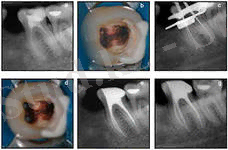

Балаларда ұлпаның анатомиялық-физиологиялық ерекшеліктері ұлпа қабынуы ағымының өзіндік шарттарына себепші болады және емдеуде кейбір қиындықтар туғызады. Бала жасында (пульпа) ұлпа камерасының өзіндік өлшемі болады. Түбір өзектері және апикалді кеңістік кең болады. Ұлпа көп мөлшердегі лимфа қан тамырлары мен нерв талшықтары бар борпылдақ байланыстырушы тін (ткань) болып табылады. Мектеп жасына дейінгі балалардағы сүт тістердің ұлпасындағы қабыну процесінің ерекшеліктері сонда, олар серозды қабынудың іріңді түріне тез ауысады. Кейін жедел периодонтитпен аскынған созылмалы гангренозды пульпитке өтуі болып табылады.

Балаларда пульпитті емдеу тәсілін таңдауда тұрақты және сүт тістердің түбірлерінің сорылу мерзімін ескеру керек. Сүт тістердің түбірлерінің толық қалыптасуы сүт тістер түбірлерінің қалыптасып болғаннан кейінгі 3-4 жылдан соң және шығып болғаннан кейін 4-5 жастан соң аяқталады. Балаларда жұқпалы аурулармен ауырған немесе созылмалы аурулармен асқынған тұрақты тіс түбірінің қалыптасуы олар шыққаннан кейінгі 5-6 жастан кейін (кейде 7 жаста) аяқталады

Рентгендік тексеру емдеу әдісін дұрыс таңдау мен сол арқылы асқынулардың алдын алуға мүмкіндік береді. Тістердің түбірлерінің қалыптасу және сорылу мерзіміне сүйене отырып пульпитті емдеуде көрсетілімдерді таңдауда мышьяк пастасын қойғаннан кейінгі перипикалды аймақта әр түрлі асқынулардың алдын алу үшін сүт азу тістерін 8-9 жаста жұлу керек. Сүт күрек тістерде пульпит некроз және ұлпаның өлуі салдарынан өте сирек кездеседі. Олар созылмалы периодонтитпен асқынады. Ұлпа қабынуын емдеу әдісін таңдауда бірінші кезекте қабынудың таралуы және түбір өзегін сипаттайтын анатомиялық талаптан кейін тістің жағдайын және баланың жалпы жағдайы маңызды болып табылады. Ұлпаны жасанды некрозды шақырып немесе иньекционды жансыздандыруды қолданып жансыздандырады (ұлпа қабынуын девиталды және виталды емдеу әдістері) .

Жедел пульпитті емдеу

Сүт тістердің ұлпасының жартылай қабынуында негізгі емдеу әдісі ұлпаның сауыт бөлігін ампутациялау болып табылады. Виталды ампутация - көрсетілімдеріне алдымен дамуы әлі бітпеген тістер жатады. Түбір дамуы бітпеген немесе шамалы кірген, тарылған түбірлері бар үлкен азу тістерге девиталды ампутацияны қолдануға болады. Девиталдаушы құрал ретінде сүт тістерге мышьяк ангидридін қолданбау керек. Оның орнына әлсіз жәй әсер ететін девиталдаушы құралдарды қолдануға болады. Тісжегілі (кариозды) қуысында оны жеті күн шамасында қалдырады. Девиталды ампутациядан кейін ұлпа шолақ бөлігін (культясын) мумифицирлейтін пастамен жабады (резаорцин-формалинді) және тісті пломбалайды. Жалпы пульптті емдеуде барлық ұлпаны алып тастау керек (экстирпация) осы араласуды девиталдаудан кейін түбір өзегін химиялық және механикалық дайындау үшін оларды сорылмайтын (нерассасывающий) пастамен толтырады.

Созылмалы пульпитті емдеу

4 жасқа дейінгі жоғарғы күрек тістерде және төменгі үлкен азу тістерде дамитын, туа біткен тіс тінінің даму кемістігі бар тістерде бірінші реттік созылмалы пульпиттер басым болады. Бұл жағдайда витальды ампутацияны қолданады. Өршіген біріншілік созылмалы пульпитте бұл жаста тіс түбірлері қалыпталмаған тұрақты тістердің дайын үлгісі (заготовкасы) максималды жақындаған. Ұлпа камерасының қуысы кең, түбір өзектері кең және қысқа болады. Ұлпа тіні морфологиялық және функционалды толмаған пульпитті емдеу ұлпа мумификациясымен 3 қабылдауда девиталды ампутацияны қолданады. 4-6 жаста жедел пульпит пайда болады. Тіс түбірлері бұл кезде қалыптаспаған (тікелей және тікелей емес жабық ұлпалар) . Балаларда экстирпация әдісімен пульпитті емдеу Көрсетілімдері: жедел іріңді, созылмалы гангренозды, периодонтта фокальды өзгерістері бар барлық пульпиттер және барлық түбір ұлпасын сақтауға мүмкін болмағанда қолданылады. Балаларда тек түбірдің өсуі аяқталғанан кейін және түбір ұшты кеңістік қалыптасқанан кейін толық алып тастайды. Уақытша тістерде тек қалыпталған түбірлерді алып тастайды.